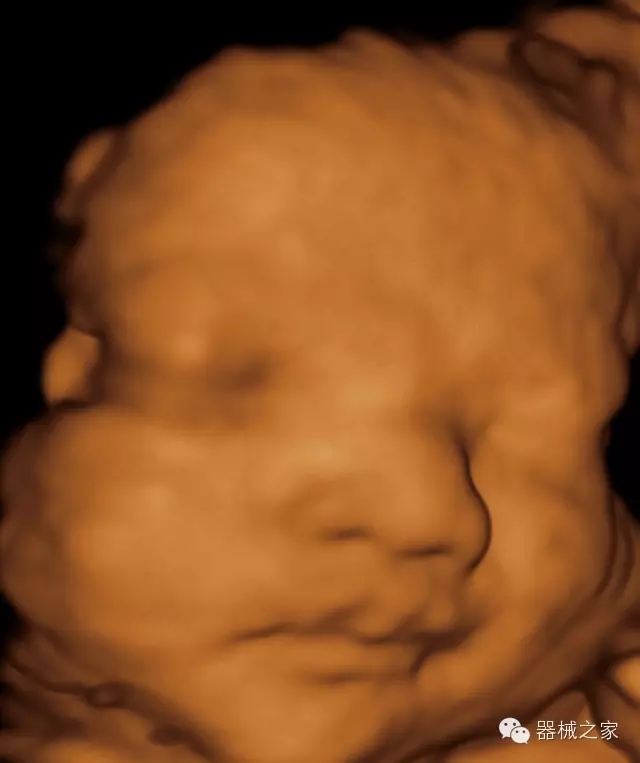

臨床圖片賞析

·高效3D/4D成像技術:高速的4D幀頻,豐富的3D成像模式,智能斷層切片功能;